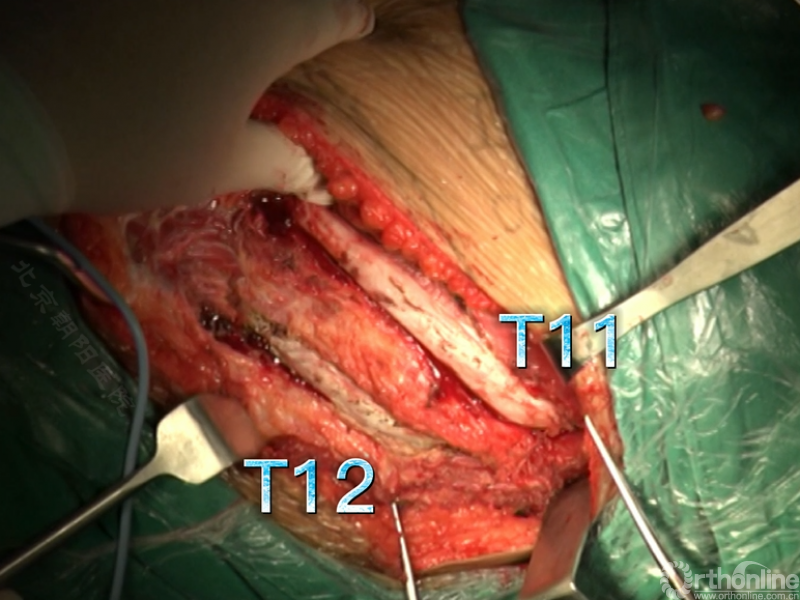

经近端需内固定的椎体(T11)相对应的肋骨表面做一弧形切口,分离浅层软组织直至肋骨表面的多层肌肉组织,切口止于脐的远端偏外侧。

骨膜下环形剥离完整显露肋骨。

切开第11肋骨肋软骨的连接部,并将肋骨靠近脊柱的部位切断。

同理将第12肋骨摘除。

由第12肋前端软骨部位进入腹膜后间隙,可以见腹膜后脂肪。